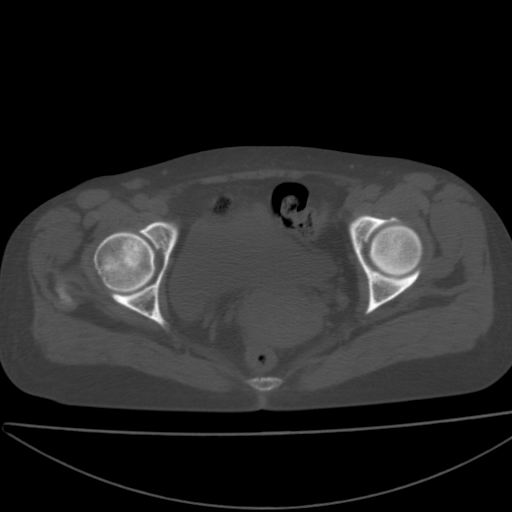

以下是引用xiaoniu在2008-9-6 8:22:00的发言:[br]右侧股骨颈囊性低密度,囊壁边缘硬化,中年妇女,首先考虑:骨囊肿。其次考虑动脉瘤样骨囊肿。[br][br][br][本贴已被 xiaoniu 于 2008-9-6 9:04:54 修改过]